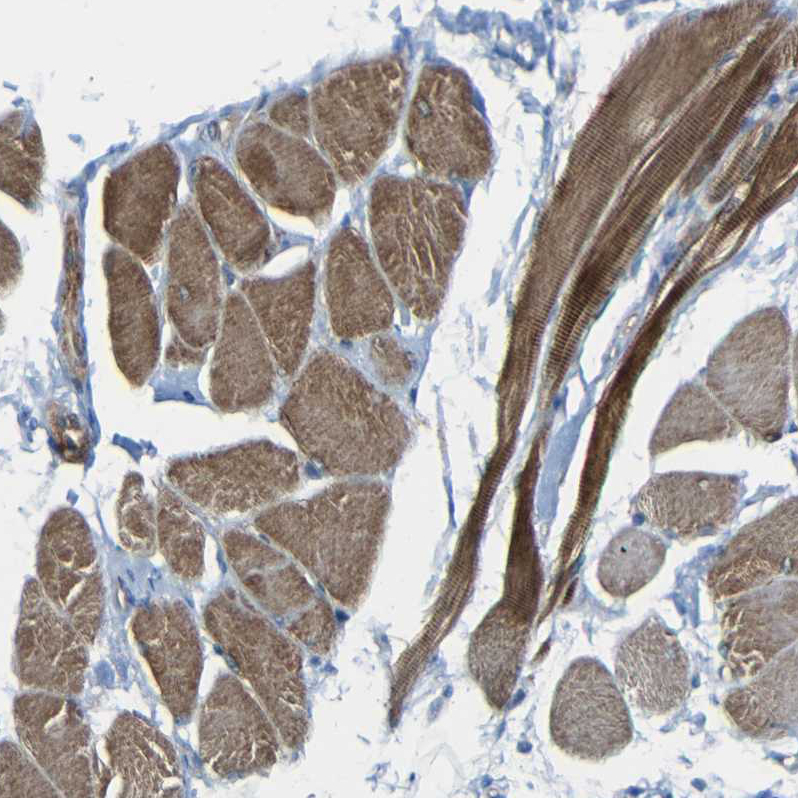

Immunohistochemical staining of human Cerebral cortex shows moderate granular cytoplasmic positivity in neuronal cells.